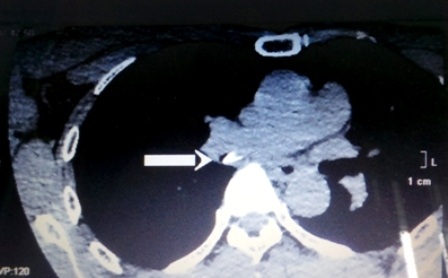

Qua chẩn đoán hình ảnh, bác sĩ phát hiện trong đường thở của bệnh nhân có vật cản quang trong phế quản và ứ khí trong thùy dưới phổi phải. Ngay sau đó, bệnh viện tiến hành nội soi, hình ảnh thám sát phát hiện dị vật là một chiếc xương cá đang gim chặt vào phế quản góc thùy dưới phổi phải. Chiếc xương cá (có kích thước 0,2 x 0,5cm ) nhanh chóng được gắp ra ngoài. Sau nội soi gắp dị vật, tình trạng sức khỏe của bệnh nhân nhanh chóng bình phục.

Việc chẩn đoán, can thiệp hóc xương ở những ca bệnh khó phải dựa vào nhiều phương tiện chuyên môn